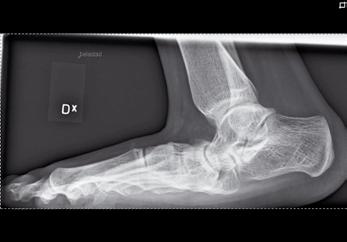

Figur 1a-d. Belastade fotbilder hos patient med bilateral spastisk cerebral pares med tydlig abduktion av framfoten på höger sida(fig 1a), där man på sidobilden (fig 1b) ser ett tydligt ”midfoot break” Patienten går med tåisättning på båda fötter och uppvisar tydlig hallux valgus bilateralt. Fig 1c visar peroperativa röntgenbilder, där laterala delen av foten förlängts genom insättning av strukturellt bengraft någon centimeter från leden mot cuboideum. Fig 1 d visar MTP I artrodes med stiftfixation på samma fot.

Figur 2a och b. Patient med valgusbelastad fot och hallux valgus interfalangeus Postoperativ bild där calcaneus förlängts så att framfotsabduktionen försvåras. Stortån har åtgärdats genom en kilosteotomi på grundfalangen.

och övriga framfoten glider på det rundade talushuvudet varvid mediala ligamentapparaten successivt blir alltmer uttänjd (fig 1) samtidigt som peroneusmuskulaturen bidrar till abduktionsställningen. Vanligen står inte hälarna inte så kraftigt i valgus inledningsvis, men detta kommer ofta med tiden. I och med att framfoten vid belastning pekar mer lateralt minskar plantarflexorernas möjlighet att hålla emot underbenets strävan framåt över foten, och risken för knäande gång ökar därvid ytterligare. Speciellt hos barn med sämre gångförmåga tillkommer med tiden också ofta en utåttorsion av underbenen och ibland även en valgusställning i själva talocruralleden. En idag vanlig operationsmetod, för att på barn med måttlig framfotsabduktion motverka naviculares lateralglidning på talus, är en förlängningsosteotomi på calcaneus 1-2 cm bakom calcaneocuboidleden. Efter att osteotomispalten bänts isär införes en kil av trikortikalt cristaben eller annat strukturellt bengraft (fig 1c, 2b). Är detta otillräckligt (som t.ex. vid samtidig ledlaxitet) kan foten stabiliseras ytterligare genom talonaviculär artrodes. För de mest felställda och rigida fötterna kan trippelartrodes bli aktuell.

Stortåproblem är vanliga hos de lite äldre barn som fortsätter att gå med tåisättning av foten. Vanligen är felställningen störst på MTP-nivå (fig 1a), men ibland består den huvudsakliga prolemet av en hallux valgus interfalangeus med clavusbildning motsvarande IP-leden (fig 2a). För att nå bestående resultat av hallux valgusingrepp kan det vara klokt att överväga MTP I artrodes (fig 1d) eftersom felställningen annars tenderar att återkomma om barnet fortsätter att gå med tåisättning.